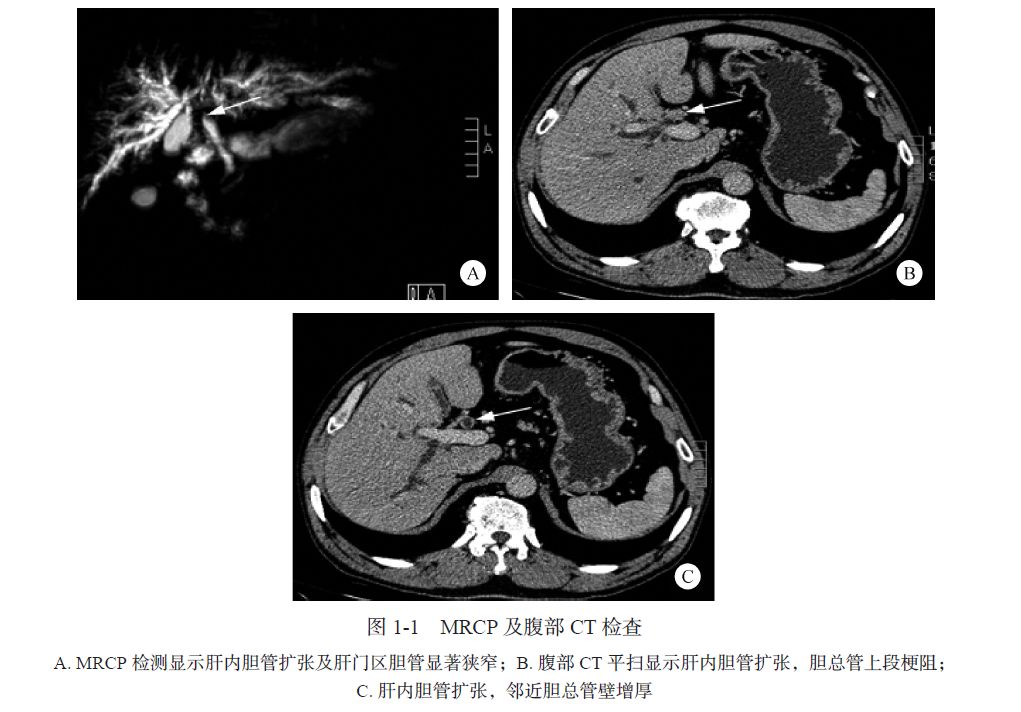

常值< 15 IU/ml),CA19-9 671.92 U/ml(正常值<37 U/ml)。MRCP 扫描:肝内胆管扩张及肝门区胆管显著狭窄(图1-1A)。腹部CT 平扫:肝内胆管扩张,胆总管上段梗阻(图1-1B、C),邻近胆总管壁增厚(见图1-1C),提示肝门胆管癌(HCCA)可能。